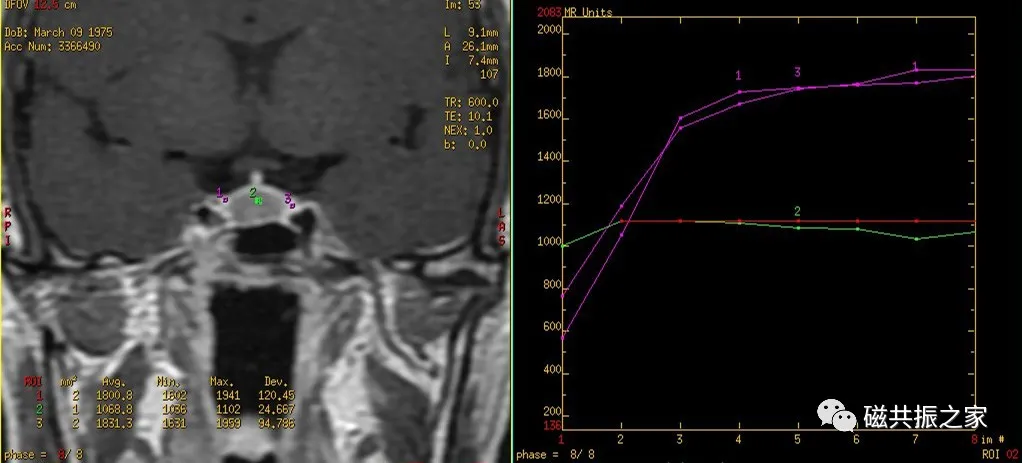

扫描后的图像做动态增强曲线后处理分析。

根据垂体的血供关系,垂体增强化顺序为垂体漏斗部及后叶、垂体柄、垂体前叶。

垂体无血-脑屏障,在注射造影剂后的早期即可发生强化,而大多数的微腺瘤由垂体的门脉系统供血,其强化比正常垂体慢,在注射造影剂后早期表现为弱强化或不强化,延迟期较正常垂体强化或不强化;但也存在少数的微腺瘤由颈内动脉直接供血,在增强早期也会发生强化。

据部分文献报道在注入对比剂早期即30-90S和1-3min为垂体微腺瘤的最佳对比时间。